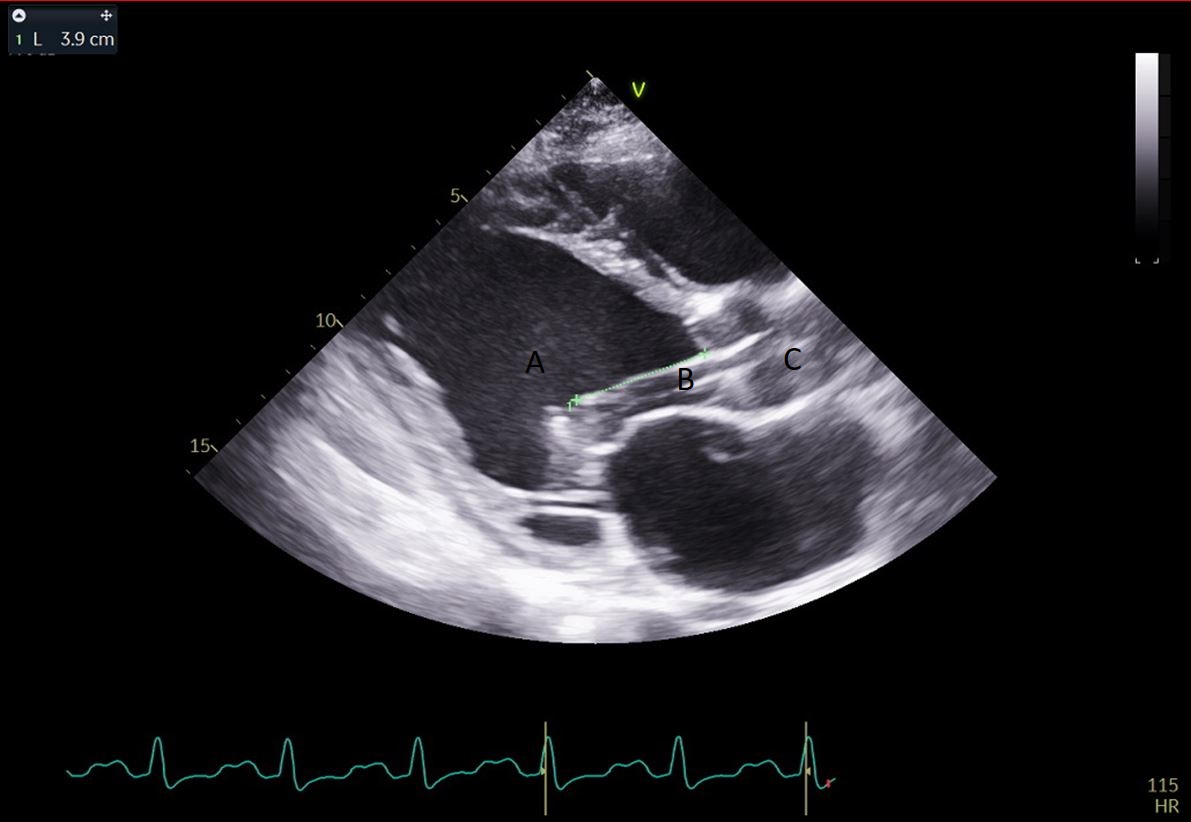

Both TTE and TEE can help with ideal positioning of the Impella (Figs. 5,6). The distance from the aortic valve to the Impella inlet should be measured. This should ideally be 3.5–4 cm for all Impella devices except for the Impella 5.5 for which it is 5 cm [15] (Fig. 7). The outlet should be 1.5–2 cm above the sinuses of Valsalva. The catheter should be angled towards the LV apex and away from the septum and mitral valve. The positioning of both the inlet in the LV cavity and the outlet above the aortic valve should be confirmed. Color flow doppler imaging can help confirm this positioning as a mosaic pattern will be visualized near the inlet and outlet ports on spectral doppler (Fig. 8). Real-time 3D echocardiography can also be used to help in visualizing Impella positioning relative to other anatomical structures (Fig. 9). After placement of the Impella, the aortic and mitral valves should be interrogated for any new or worsening regurgitation or dysfunction [16]. TEE can also help identify additional complications of Impella placement including pericardial effusion or LV free wall rupture [17].

Fig. 7.A parasternal long axis view on a transthoracic echocardiogram. The distance from the Impella inlet to the aortic valve is measured and noted to be 3.9 cm. (A) LV Cavity. (B) Impella. (C) Ascending aortic root.